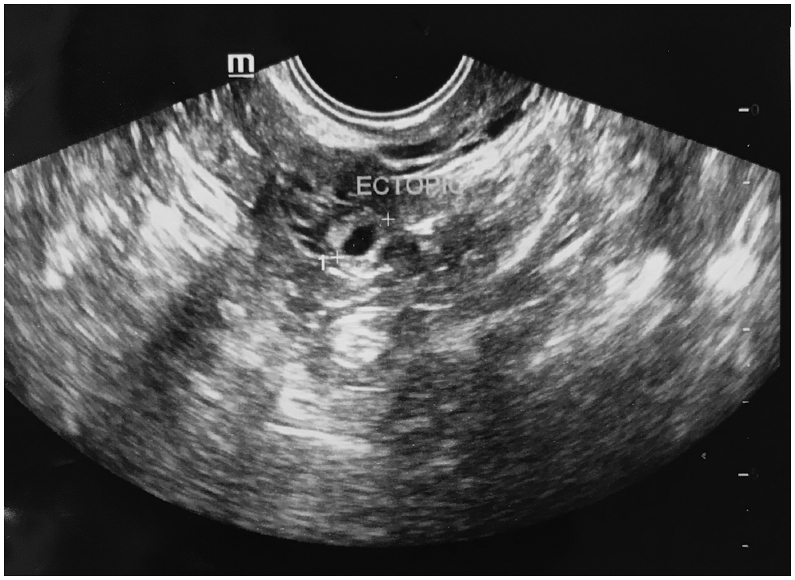

Pregnancy or positive IVF status was said to have occurred when the β-hCG level was ≥50 IU/L. If the day 16 β-hCG test was positive, but 200 mIU/mL, a second β-hCG concentration was performed 48 h later with an aim to assist in predicting a viable intrauterine pregnancy or to assist in evaluating a possible EP. An EP was defined when a pregnancy was confirmed by β-hCG and accompanied by sonographic visualization of an extrauterine gestational sac (Fig. 2; including any heterotopic gestations) or with an empty uterine cavity and increasing hCG level10 However, the first β-hCG value was considered for the statistical analysis.

Fig. 2.

Transvaginal picture of an ectopic pregnancy.